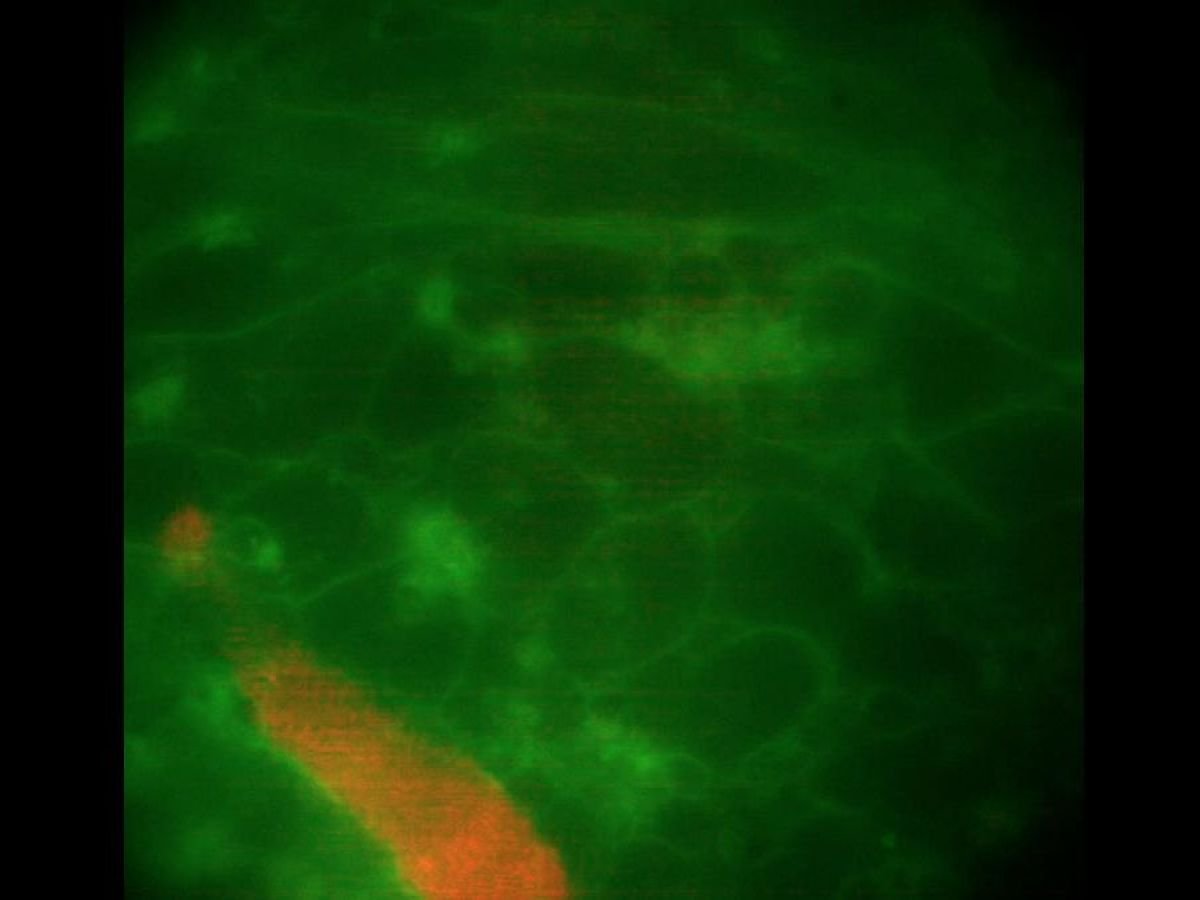

Os pesquisadores descobriram então que uma proporção significativa (85%) desses macrófagos estabeleceu conexões elétricas diretas com células cardíacas vizinhas. Usando marcadores fluorescentes, eles também perceberam que os macrófagos pulsavam em sincronia com as células do músculo cardíaco, causando batimentos visíveis a olho nu.

Crédito do vídeo Aitor Aguirre et al.